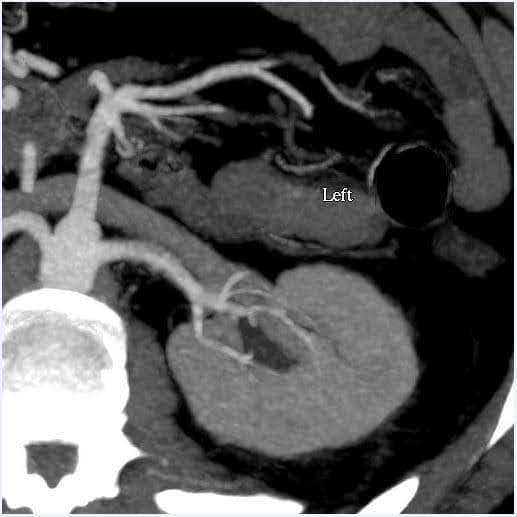

Böbreklerin büyüklüğünün yanı sıra böbrek damar sistemi ve toplayıcı sistemdeki anatomik varyasyonları değerlendirmek için karın BT anjiyografisi yapıldı (Şekil 1). Bu durumda, böbreklerin tahmini hacmi% 10'dan daha az bir tutarsızlığa sahipti, bu da fonksiyonel test merkezimiz için son sınırdır. Donörde bilateral tek renal arter ve tek renal ven vardı. Renal pelvis veya üreterlerde herhangi bir anormallik kaydedilmedi. Sol böbreğin üst polünde 2 cm'lik basit benign görünümlü kortikal kist görüldü. Böbreklerde taş veya anormal kitle saptanmadı.

Şekil 1. BT anjiyografi karın (böbrek). Sol: sol tarafta tek renal arter ve veni gösteren eksenel görünüm; Sağ: koronal görünüm Sol böbrek.